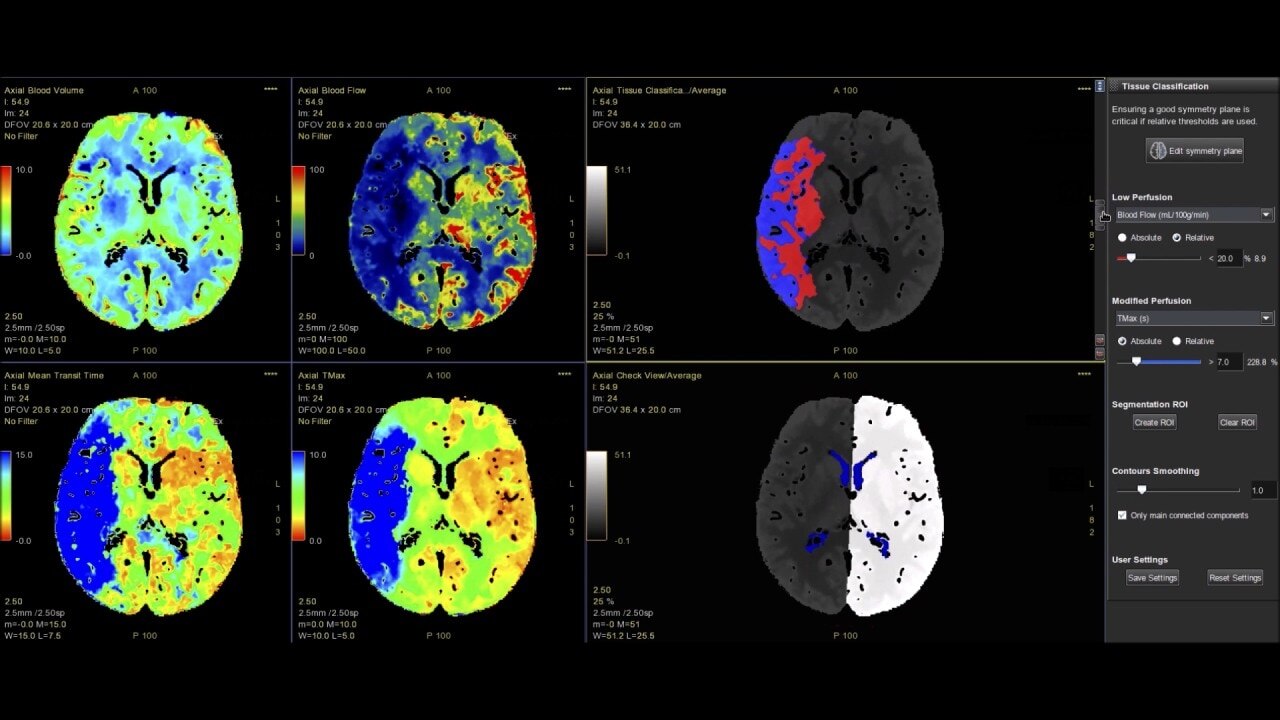

Brain stroke protocol

• Image Registration to minimize the effects of patient movement

• Bone Removal to remove the cranium automatically from the dataset

• Deep Learning brain ventricle segmentation to prevent ventricular matter inclusion in quantitative results and improve visual inspection of the maps

• Automated selection of arterial input and venous output. Both can be easily adjusted if needed.

• Automated generation of all functional maps: Blood Flow, Blood Volume, Mean Transit Time, and Transit Time to IRF Peak (Tmax)

• Automatically define the symmetry plane to be used for mirroring ROIs and relative thresholds

• Tissue Classification enables the visualization of regions that are segmented from absolute or relative values, customizable thresholds and user selectable input maps

• Mismatch volume and ratio are calculated from the modified perfusion volume and low perfusion volume ROIs